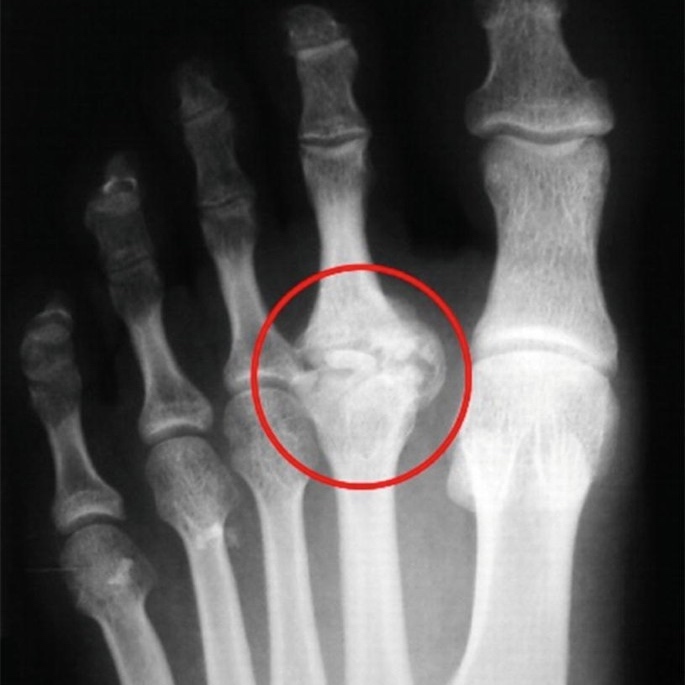

Metatarsalgia

A burning sensation or sharp pain in the ball of the foot when walking or running.

Goal: Offload the forefoot

How: Optimising calf flexibility and ankle mechanics to reduce the pressure peak at the forefoot.